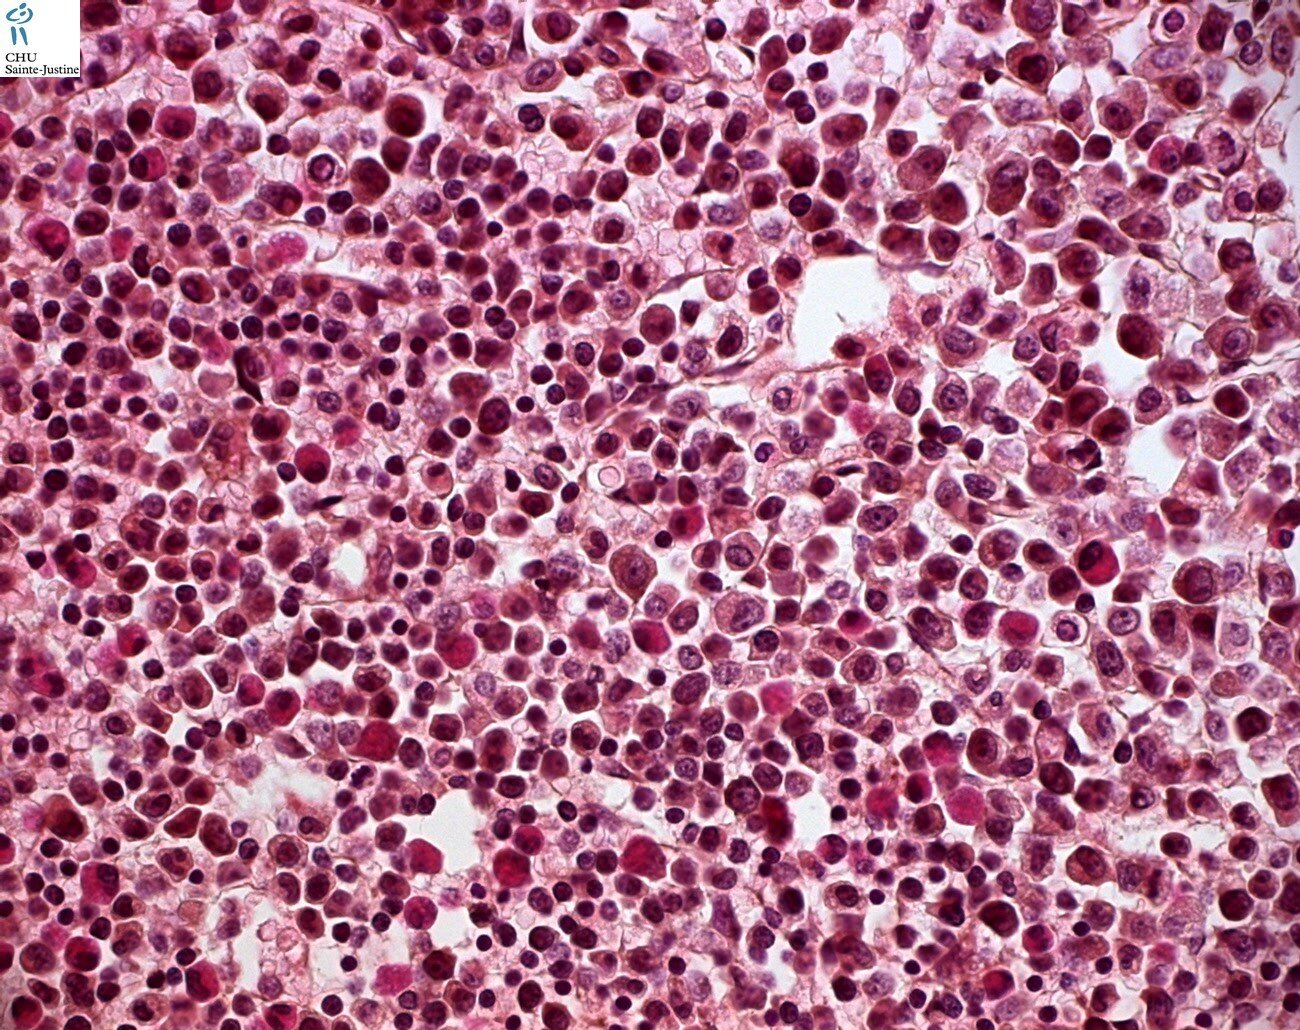

Morphology